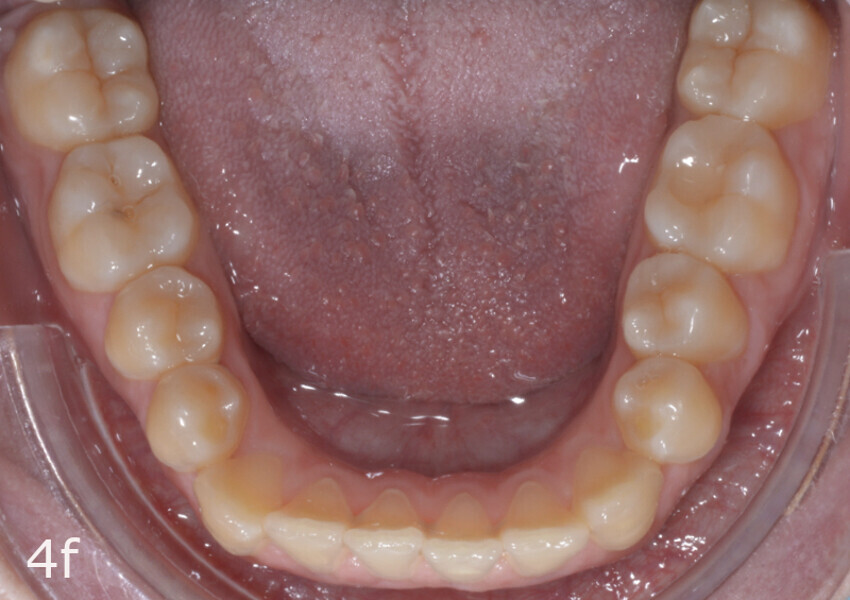

The 23-year-old dolichofacial female patient complained of not being able to chew properly. Facial examination showed a convex profile, an enlarged lower facial height, and a skeletal Class III malocclusion (Figs. 1–3). Intra-oral examination revealed an Angle Class III right subdivision malocclusion, anterior open bite, no overjet and a maxillary dental midline deviated about 3 mm to the right compared with the mandibular dental midline (Fig. 4). The panoramic radiograph confirmed previous extraction of the maxillary right first premolar and the presence of all four third molars (Figs. 5 & 6).

The total treatment time was 15 months. An Angle Class I relationship was established along with adequate anterior and canine guidance, establishing a functional occlusion. This not only ensures optimal masticatory function but also protects the teeth and the temporomandibular joint from excessive force. Maxillary and mandibular fixed retention were installed at the end of the treatment (Figs. 13–19).